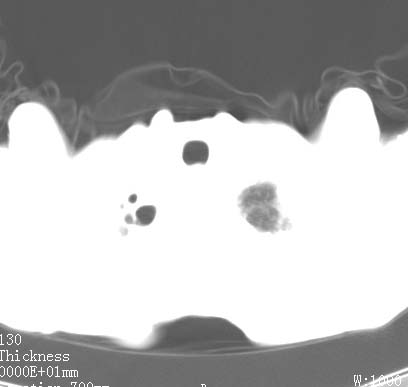

病人女 60岁 咳嗽 气促十余天,大叶性肺炎.

右肺上下叶均见 大片状密度增高影,边界清晰,其内可见支气管充气征,气管支气管通畅。纵膈略向右移位,其内无肿大淋巴结影。首先考虑炎性病变。不排除一些特异性的炎症。不知道发烧吗??wbc高吗??建议治疗后复查!!

看影响还是首先考虑炎性改变,建议实验室检查,还有要警惕炎性肺泡癌,具有的枯枝征象。

右肺感染性病变(大叶性肺炎可能);建议抗炎治疗后复查。

看影像还是首先考虑炎性改变,建议实验室检查,还有要警惕炎性肺泡癌,具有的枯枝征象